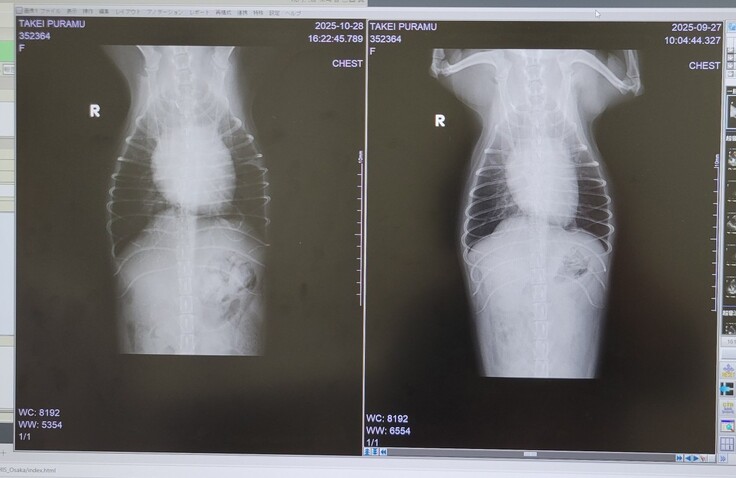

15日の失神後は特に再発もなく過ごせておりましたが、咳の回数が増えてきていたので、28日の夕方、ちょうど薬の追加購入のタイミングでレントゲンで状況を見てもらうこととしました。

すると、術後三カ月検診時よりも少し心臓が大きくなっており、加えて胸水も少し発生していることがわかりました。

左が今回です。少し、丸くなっています。幸い、肺水腫は見当たりませんでした。